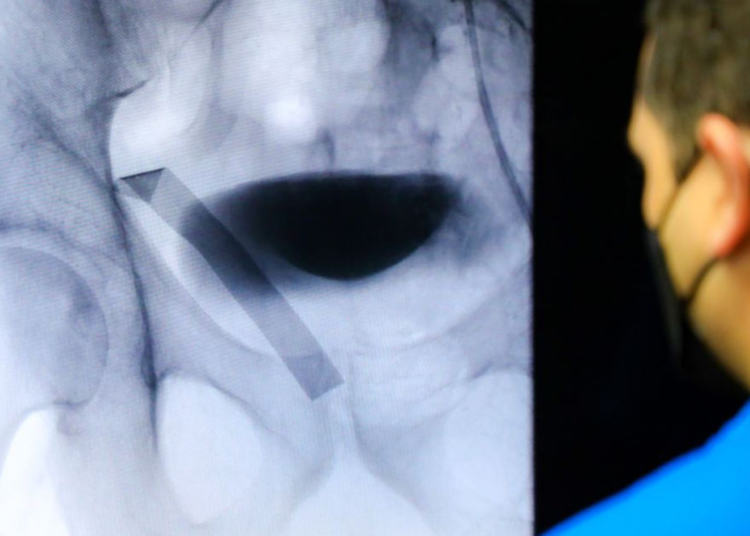

El implante de la válvula vía TAVI consiste en introducir un dispositivo cardiaco dentro de la válvula natural del paciente -que está dañada- a través de una artería periférica, con el objetivo de recuperar el funcionamiento normal del corazón.